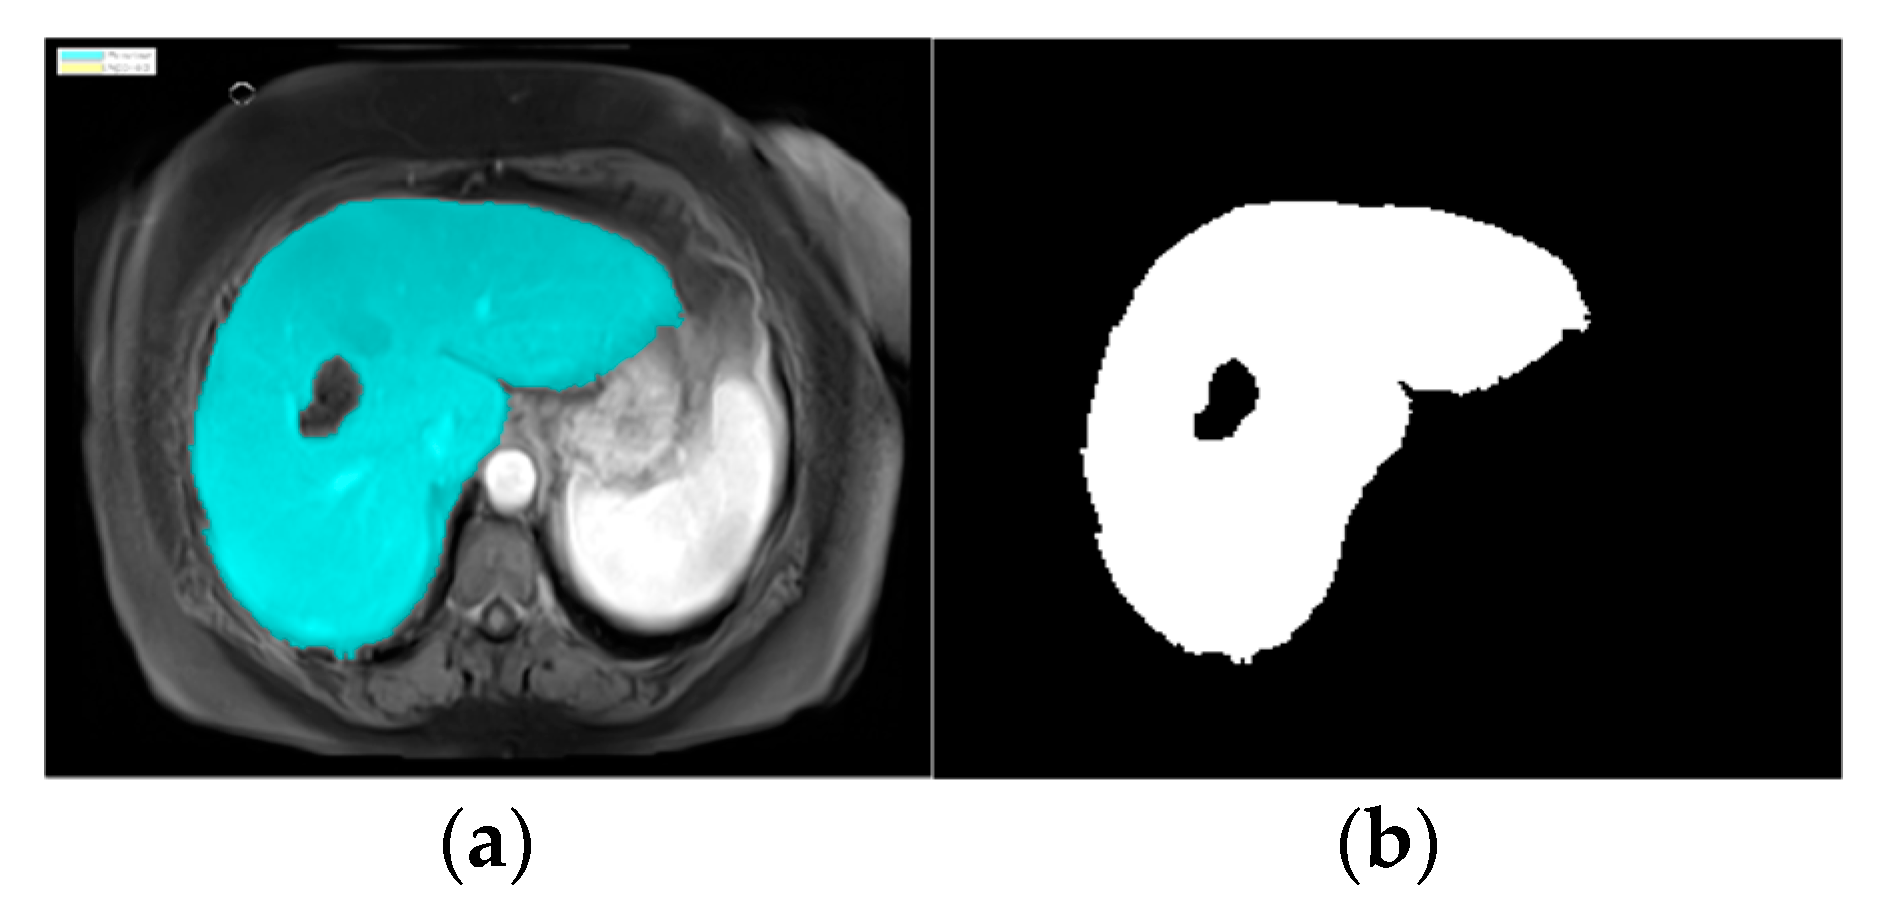

In image segmentation, we highlighted the liver in the image to easily and automatically identify it in CT scans [7]. CT images include many parts of the human body [8], so we used an image segmentation model in MATLAB (version R2024a). The process automatically proceeded to the image segmentation stage, applying the specific region of interest (ROI) function. The K-means clustering technique algorithm was used. The ROI function was used to blur, highlight, and apply a brightness threshold, where pixels with high values were considered a part of the ROIs. After identifying the liver, the image was converted to a binary image, as shown in Figure 4.

Figure 4.

Images of parts of liver and tumors in liver: (a) ROI masking and (b) liver structure in binary code.

Following the application of the watershed algorithm, we successfully segmented the liver region and converted it into a binary image (Figure 4), facilitating precise tumor detection and recognition shown in Figure 5. The implementation of 8-connectivity during segmentation further ensured the accurate identification of multiple tumors, including those with complex shapes. This approach enables the effective differentiation of tumors from surrounding tissues, leading to reliable tumor size estimations.